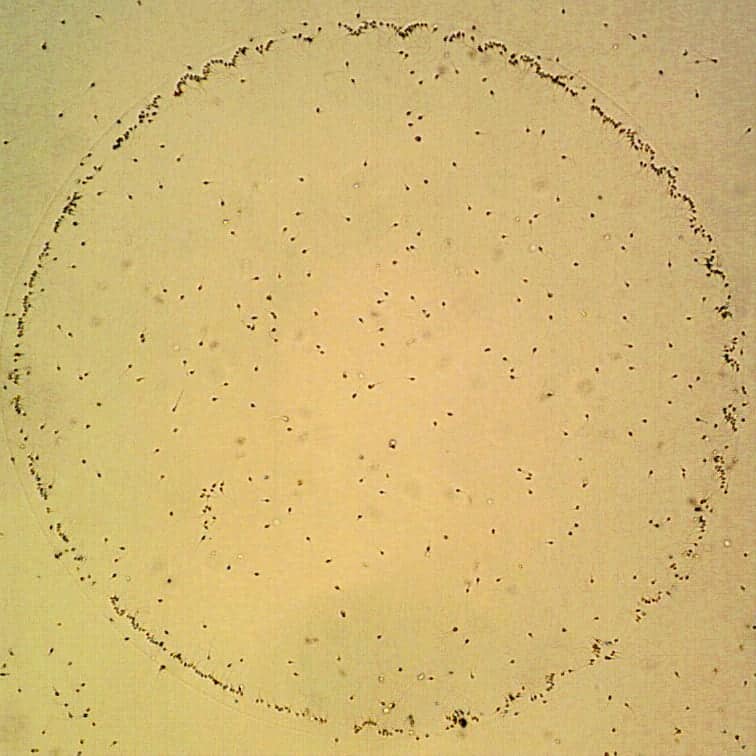

Bei dieser Methode werden die Spermien in der Petrischale inkubiert, deren Boden mit Hyaluronan benetzt ist. Für das intrazytoplasmatische Injizieren werden anschließend nur solche Spermien ausgewählt, die sich an das Hyaluronan gebunden haben. Das Hyaluronan ist ein Glykosaminoglykan (Mucopolysaccharid), das natürlicherweise als Bestandteil der Zwischenzellmasse vorkommt, die gemeinsam mit den kumularen Zellen die Eizelle umgibt. Damit das Spermium bei der natürlichen Befruchtung erfolgreich die Eizelle penetrieren und fertilisieren kann, muss es in der Lage sein, sich ans Hyaluronan zu binden. Zu einer solchen Interaktion ist nur ein reifes Spermium fähig. Durch wissenschaftliche Studien wurde nachgewiesen, dass Spermien, die zu einer Bindung an das Hyaluronan fähig sind, über eine bessere Morphologie, statistisch einen niedrigeren Anteil an chromosomalen Anomalien und eine bessere DNA-Integrität verfügen.

Der Vorteil der PICSI-Methode besteht vor allem in der objektiven Möglichkeit, ein Spermium auf Grundlage seiner adäquaten Funktionseigenschaften auszusuchen. Es ist notwendig sich dessen bewusst zu werden, dass auf Grundlage desselben Prinzips auch die Spermien bei der natürlichen Befruchtung, die im Körper der Frau geschieht, ausgewählt werden.

Defekte, wie zum Beispiel die Unreife des Spermiums, chromosomale Anomalien oder eine beschädigte DNA-Integrität der Spermien, sind häufig mit bloßem Auge selbst durch das Mikroskop nicht sichtbar und können deshalb, auch wenn ein Embryologe die Spermien auswählt, nicht gänzlich eliminiert werden. Falls also der Verdacht besteht, dass sich im Ejakulat des Mannes Spermien mit solchen Defekten befinden könnten, wird zumeist empfohlen, die Eizellen mit Hilfe der PICSI-Methode zu befruchten.

Befruchtung der Eizelle mit der Methode PICSI